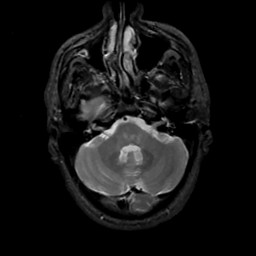

MR Study #6, March 17, 1991 -- Slice #11

[Home][Help][Clinical][Tour 1][Tour 2] Slice 11